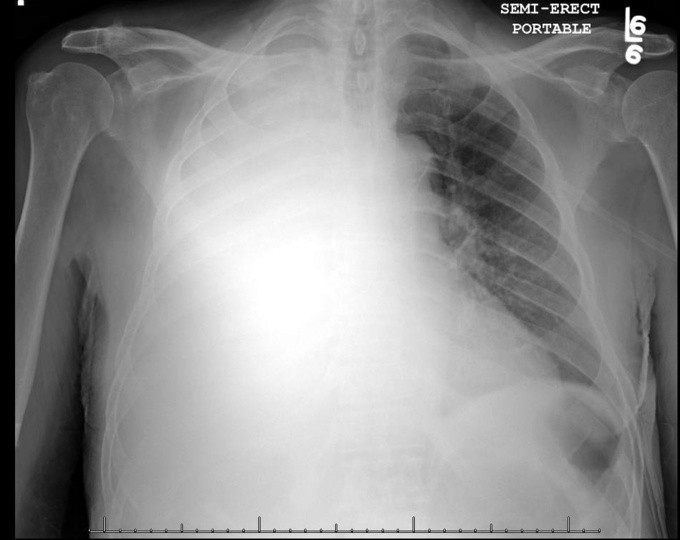

Tiến sĩ Nguyễn Văn Vĩnh Châu, Giám đốc Bệnh viện Bệnh Nhiệt đới TP HCM, cho biết kết quả CT scan sáng nay cho thấy phổi bệnh nhân này đã chuyển qua xơ hoá và mất chức năng hoạt động. Tình trạng này nghĩa là bệnh nhân sẽ chết nếu dứt ECMO (oxy hóa máu qua màng ngoài cơ thể).

Đây là bệnh nhân Covid-19 nặng nhất hiện nay, diễn biến sức khỏe rất thất thường. Bệnh nhân xác định dương tính ngày 18/3, suy hô hấp tăng dần, diễn tiến ngày càng xấu dù còn trẻ và không bệnh nền. Phổi bệnh nhân đông đặc, mẫu bệnh phẩm nhiều lần âm tính rồi dương tính trở lại.